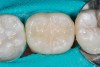

(3.) Restoration of tooth No. 31.

Figure 3